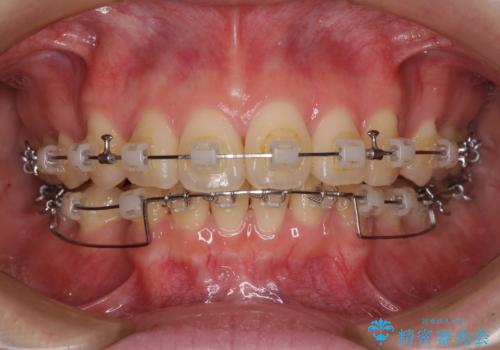

- クリアブラケット

前突間を改善するため、上顎左右の第一小臼歯を抜歯してワイヤー装置にて矯正治療を行うこととしました。

深い咬み合わせは上顎前歯を引っ込ませる大きな障害となるため、咬み合わせの改善が非常に重要となります。やや期間はかかりましたが、当初狙った通りの仕上がりで治療を終えることができました。